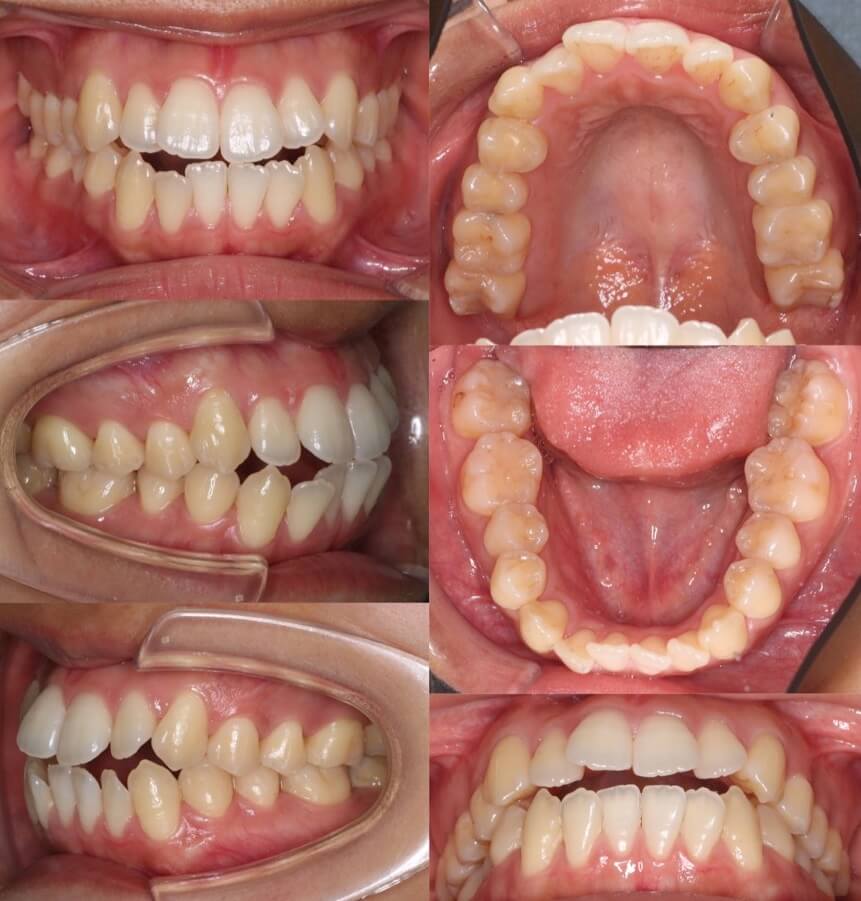

「親知らずは抜歯せず並べる」

大学生女性・マウスピース型装置・前歯傾斜型

マウスピース型装置に、最後ワイヤー装置を設置して、親知らずまで並べることに成功しました。

<症例概要> 難易度:★★★★☆

主訴:口元の突出

年齢・性別:20代女性

住まい:千葉県船橋市

症状:上下顎前歯唇側傾斜

治療方針:抜歯空隙の閉鎖(中等度固定)

治療装置:マウスピース型矯正装置(アライナー)

抜歯:上下第一小臼歯(計4本)

アライナー枚数:58+33+36+18ステージ

治療期間:2年10か月

リテーナー:上下クリアタイプ

治療費用:990,000(税込)

代表的副作用:痛み・治療後の後戻り・歯根吸収・歯髄壊死・歯肉退縮